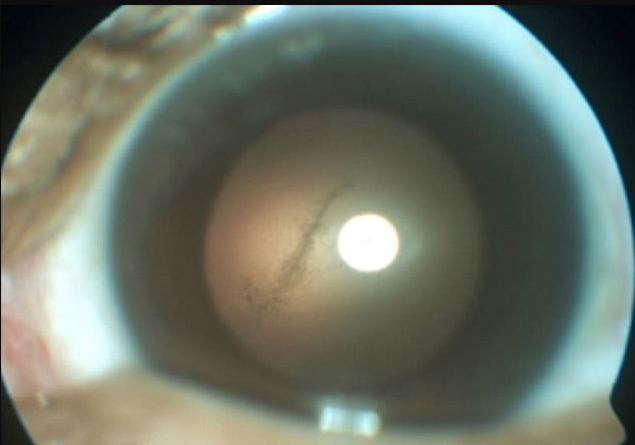

Được biết, con sán ăn não "định cư" trong khoang thủy tinh thể, phần giữa nhãn cầu mắt và võng mạc của Sam.

Hình ảnh con sán dài 3mm kí sinh trong mắt trái của anh Sam. (Ảnh: Daily Mail)

Bác sĩ điều trị cho Sam, ông Perez chia sẻ: “Con sán mà tôi gắp ra dài khoảng 3 milimet. Nó có tên là Taenia solium, thường được biết đến như một loại sán dây tồn tại trong thịt heo sống hoặc loại thịt chưa nấu chín.